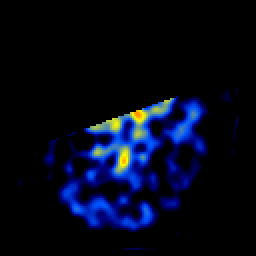

SPECT TL Study #4 -- Slice #11

[Home][Help][Clinical][Tour 1][Tour 2][Tour 3] Slice 11